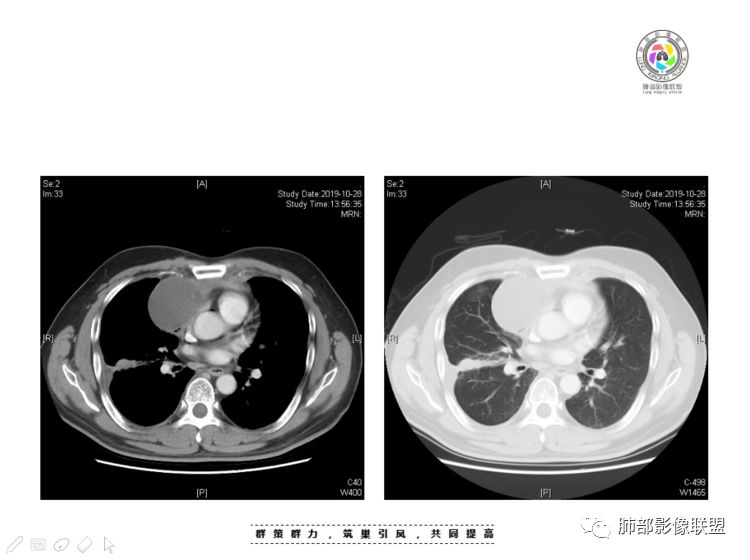

Coke with ice:囊性部分考虑包裹性积液?南边:不是积液;有间隔;张力高;而且位置有些特殊

我认为囊张力高,积液中的气体均在周围,外侧、下方,囊内有间隔:各腔密度不一致;提示:囊腔属于前纵隔,不是包裹性积液;现在的问题:囊腔与内侧的病灶是否是一体的

2、前纵隔内病灶囊实性混杂密度病灶,囊性病灶主要位于右侧,张力较高,有分隔影,囊壁右侧缘光整,病灶左侧实性部分边界不清明显强化,病灶肺瘤交界面大部分边界清楚,部分模糊。

前纵隔肿块伴囊变坏死常见以有胸腺瘤、胸腺癌、淋巴瘤和生殖细胞肿瘤。

胸腺瘤/胸腺癌:病灶内那么大的囊,常规考虑B型以上胸腺瘤,囊内有分隔影,病灶周围脂肪间隙模糊,常规考虑侵袭性胸腺瘤或胸腺癌,若侵袭性胸腺瘤,常侵犯胸膜、心包,很少累及肺。胸腺癌易侵犯胸膜、肺并纵隔淋巴结及远处转移。但肺内腺癌形态更符合原发灶。胸膜及叶间裂转移则即可来自肺,也可来自胸腺癌。